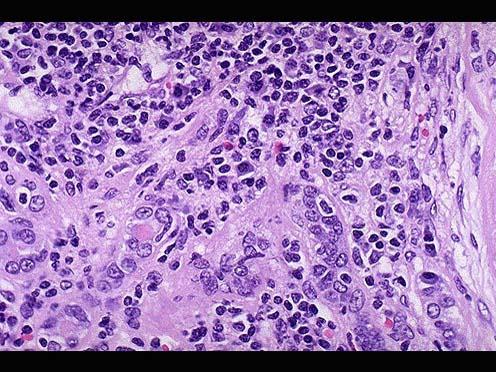

问题 患者女性,53岁,双肾缩小,表面可见不规则瘢痕,两侧改变不对称,切开,皮髓质界限不清,肾乳头萎缩,肾盏和肾盂因瘢痕收缩而变形,肾盂黏膜粗糙;巨检如图,镜下如图所示,应首先考虑的是 ( )

选项 A.高血压性肾病 B.慢性肾盂肾炎 C.急性肾小球肾炎 D.肾结核 E.慢性肾小球肾炎

答案 B